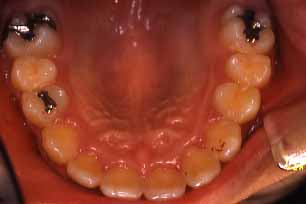

矯正前

上顎

(ミラー像)